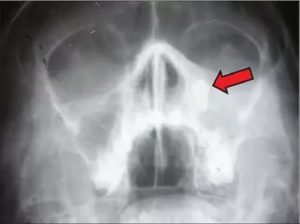

- Рентгенография более доступная аппаратная диагностика. С использованием контраста можно оценить состояние слизистой гайморовой полости, наличие полипа.

При подозрении на гайморит любой природы обязательно проводится рентгенологическое исследование. Процедура отличается неинвазивностью и доступностью. Практически в каждом медицинском учреждении можно сделать снимок носовых пазух.

Съёмку выполняют в заднебоковой, аксиальной, боковой, подбородочной и носоподбородочной проекциях. При отсутствии воспаления и новообразований полости на снимке представлены тёмными кругами неправильной формы. Если имеет место воспаление, то в полости заметны тени. Полипозный очаг выглядит как небольшое белесое пятно.